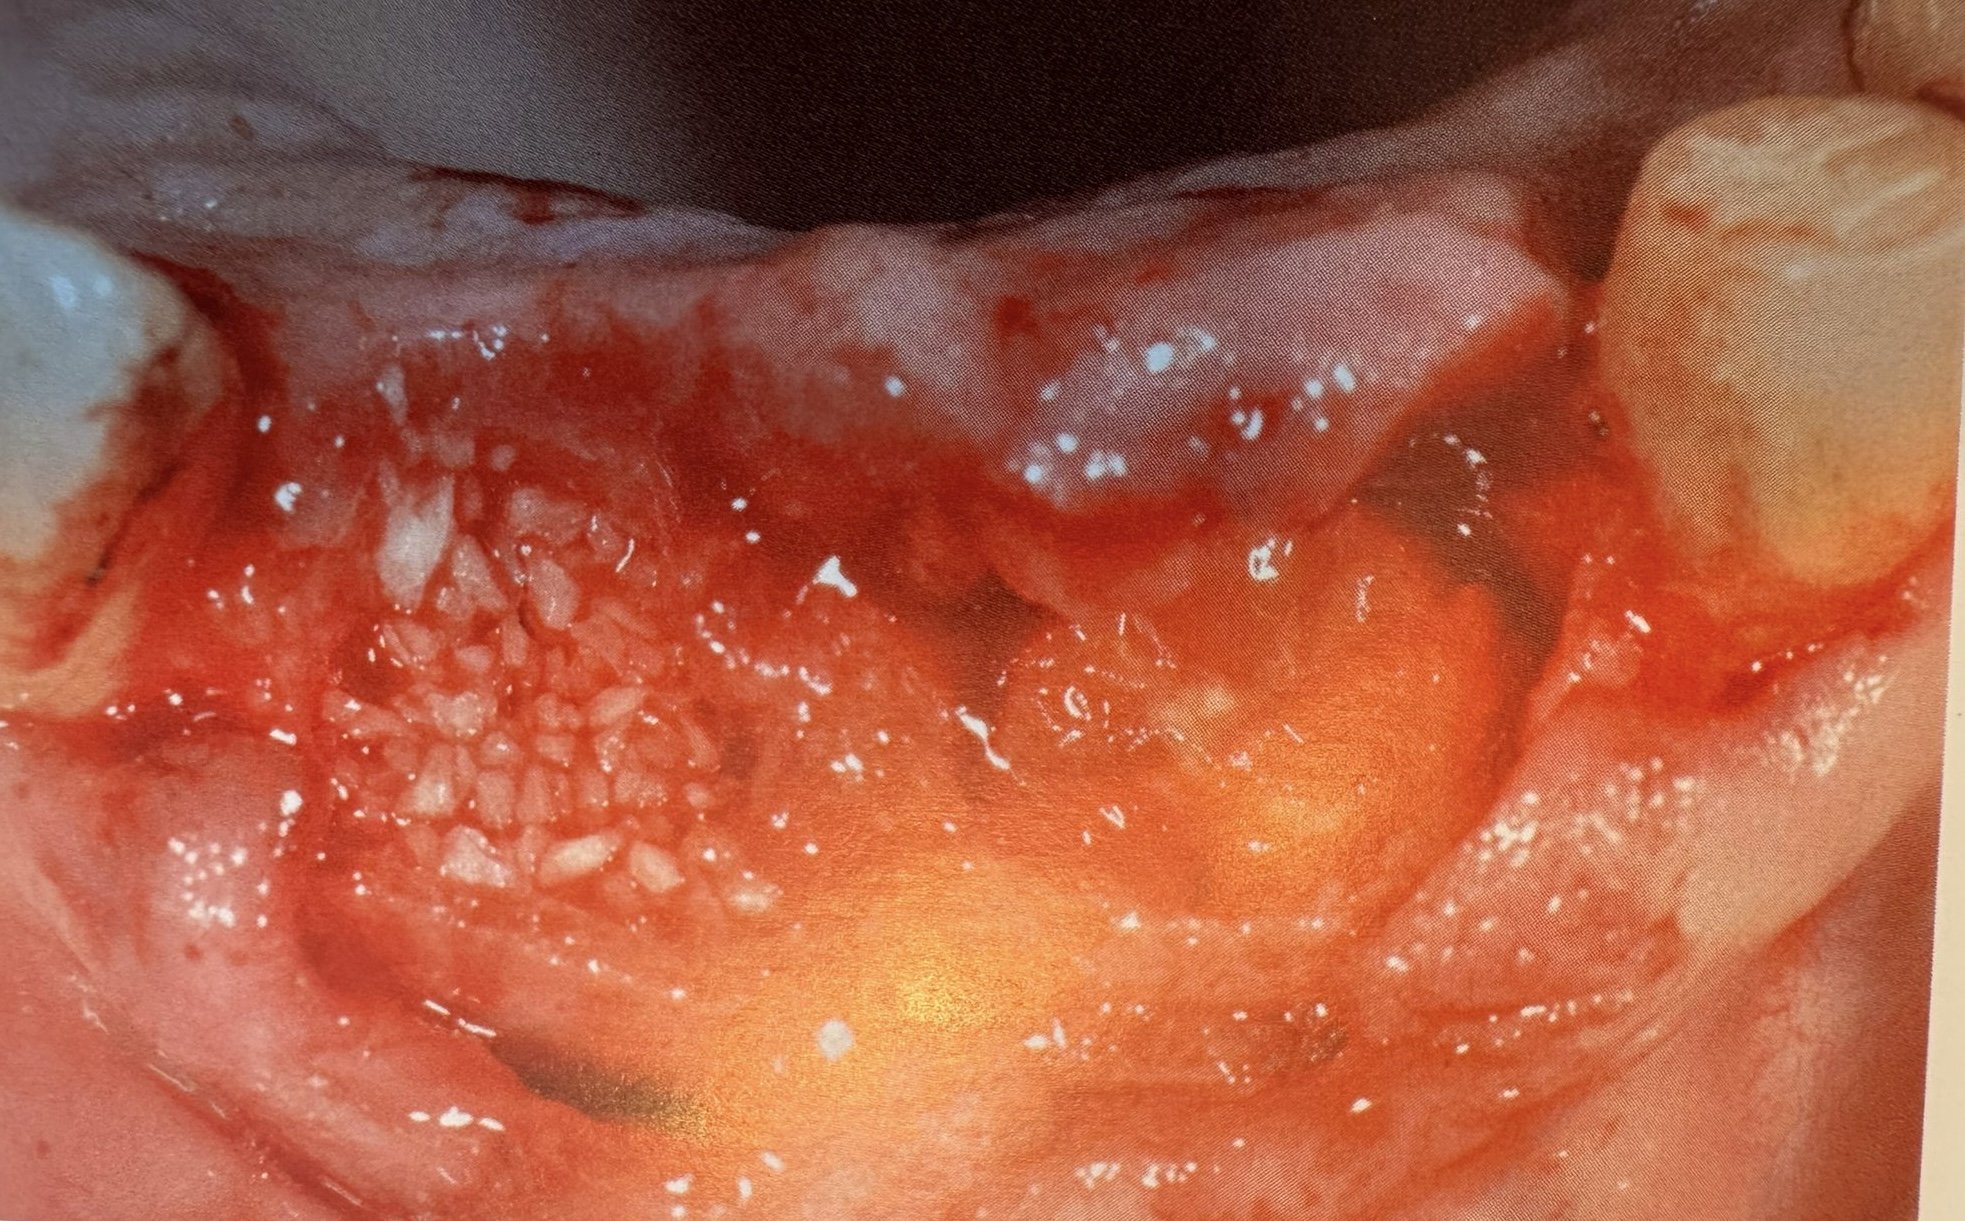

Estrazione, Rigenerazione Ossea e Riabilitazione Implantare

Ricostruzione dei colletti